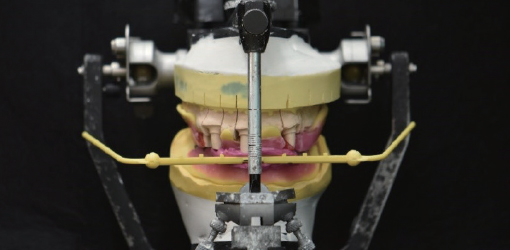

9. With the acquired POP BOW system, average mounting of the upper and lower model can be performed on the articulator

9. With the acquired POP BOW system, average mounting of the upper and lower model can be performed on the articulator